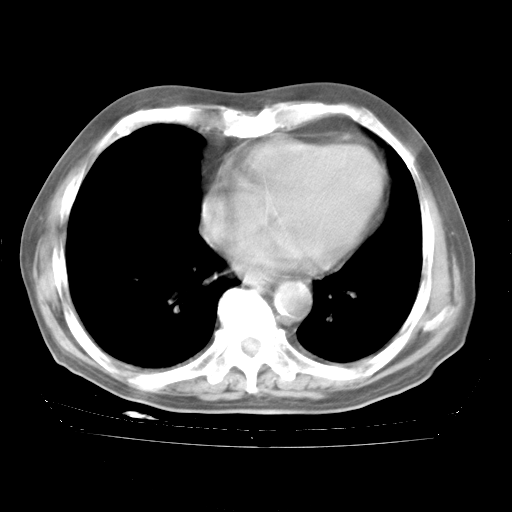

4月28日肺部CT——再次出现类似去年5月9日——磨玻璃样、间有“粟粒样”改变。